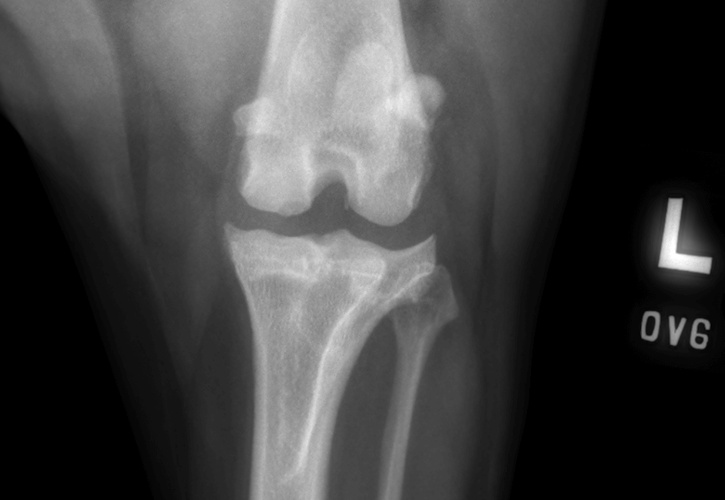

Pre-Surgical Radiographs

Orthogonal radiographs of both stifles are obtained and assessed. In the majority of cases, an effusion is visible within the stifle that demonstrates inflammation and pathology of the joint. The joint is assessed for other diseases such as osteochondritis dissecans (OCD), or neoplasia (cancer). Chronic cruciate injuries or those with concurrent meniscal damage tend to have an increased amount of degenerate changes visible on the radiographs.

OCD lesion of the canine stifle highlighted with a blue dotted line